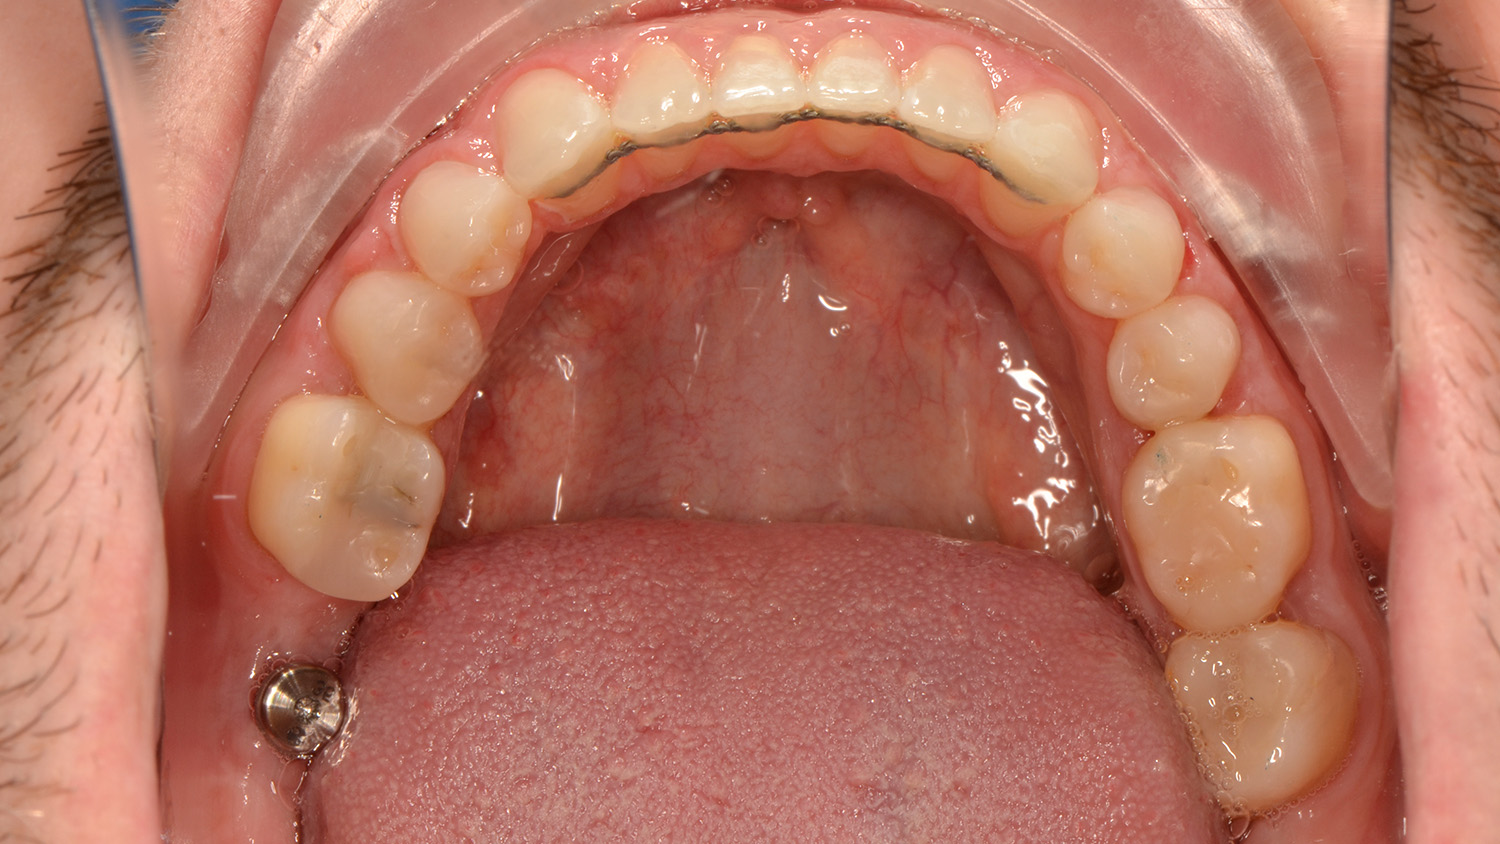

The primary goal of the treatment was to correct the transverse deficiency of the maxillary arch (>5 mm) and resolve the skeletal crossbite. MARPE was used to address this transverse issue.

Once the transverse discrepancy was corrected, treatment continued with Spark Aligners to address the vertical plane. The planned vertical correction involved extruding the upper anterior teeth, with 1.7 mm of extrusion in the upper arch, and 1.5 mm in the lower arch using attachments. To assist in bite closure, turbo bites were employed to intrude the mandibular molars.